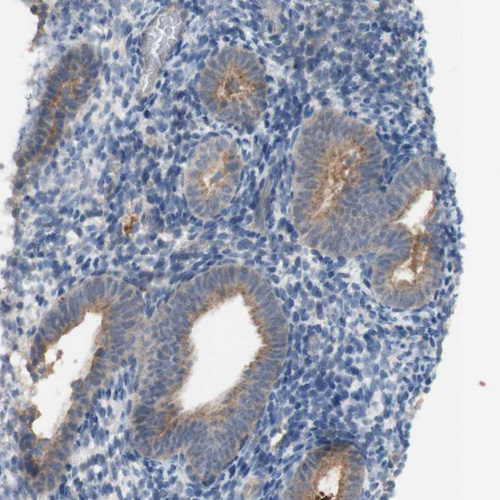

Immunohistochemical staining of human kidney shows moderate granular cytoplasmic positivity in cells in tubules.